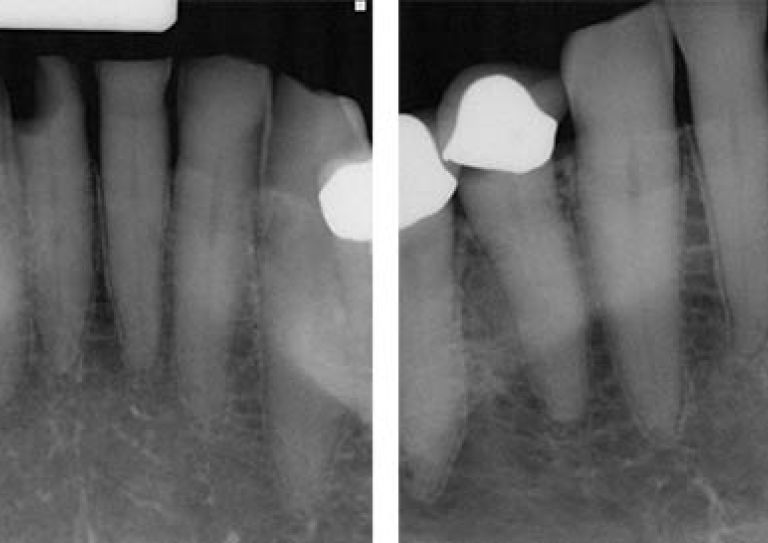

Radiograph of distal D3 approximal lesion on tooth #25. The technique known as SMART could help repair tooth damage and prevent caries without requiring multiple appointments.